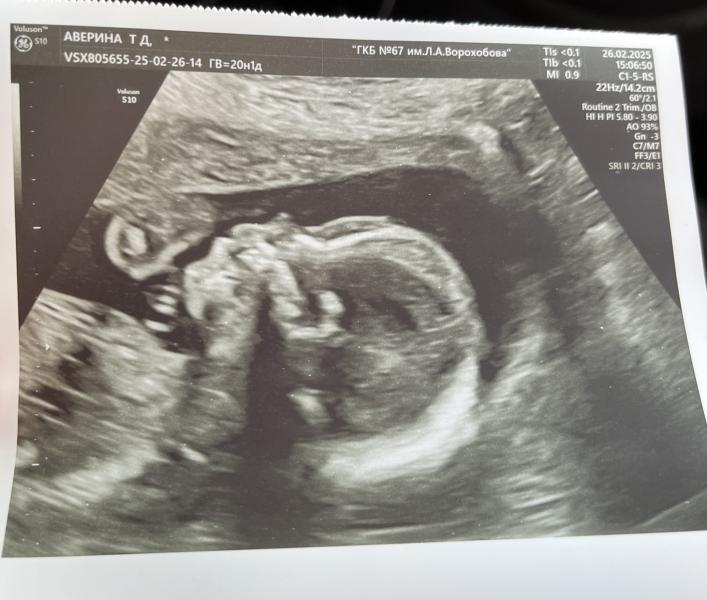

Прошли с моим малышом сегодня 2 скрининг в 67 ПЦ🩵

Срок 20.4 недели

Все у нас отлично , никаких отклонений

Снова подтвердили мальчика😄 нос у нас папин 😍